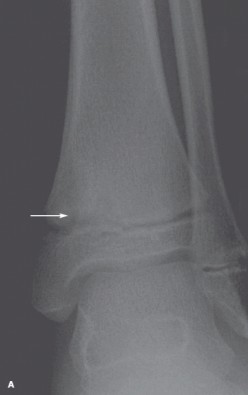

For 2 to 3 weeks, a 10-year-old boy had pain and swelling of the left ankle.